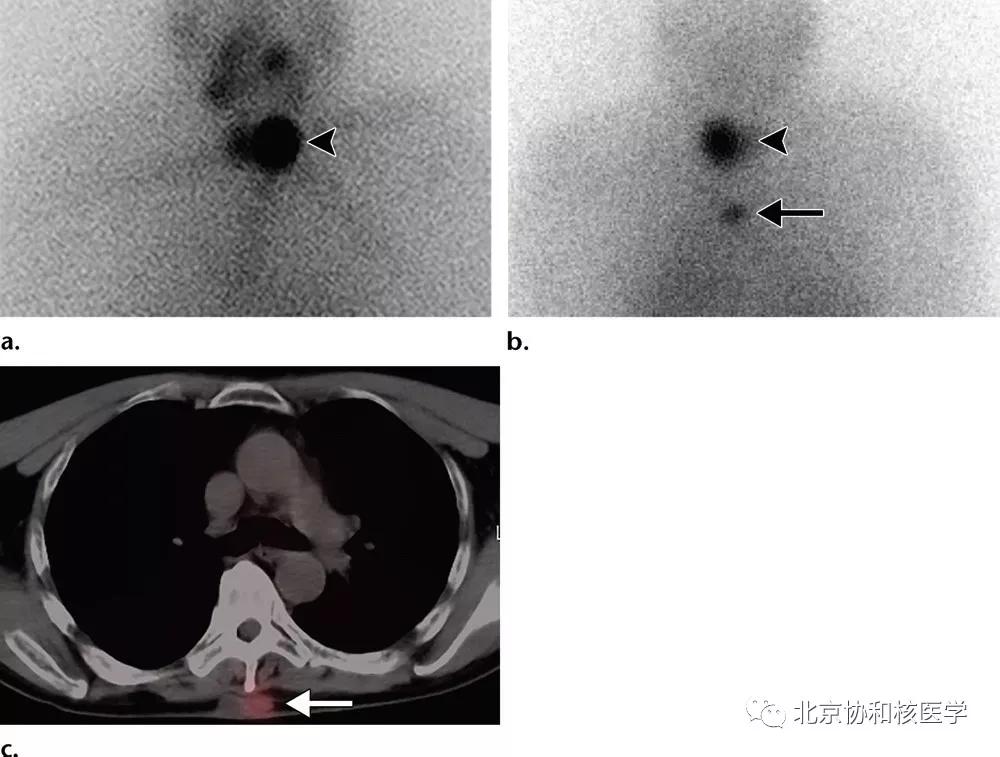

肺鳞癌所致碘摄取(后位图像),同时可见颈部甲状腺残余病灶: